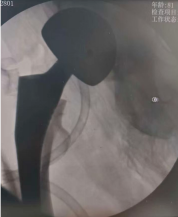

术中,团队采用微创入路,精准植入人工股骨头。手术创伤小、出血少,假体安放位置理想,为快速康复打下了坚实基础。

术后复查的 X 线片显示,两位老人髋关节置换位置均非常理想,为后续康复锻炼提供了必要条件。在医护团队的精心指导和鼓励下,两位老人术后第三天便成功下地站立、行走。